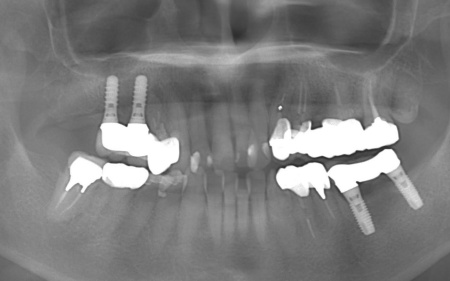

レントゲン撮影をして詳しく検査した結果、ブリッジを支えている左上の歯(第1小臼歯)は、歯根が割れていることが判明しました。

このまま放置すると、周囲の骨や歯茎に炎症が広がるおそれがあります。また、歯の状態から温存は困難だと判断しました。

以上のことから、歯根が折れた歯を抜いたうえで、欠損部位を補う治療が必要だと診断しました。

第1小臼歯に歯根破折を認めました。